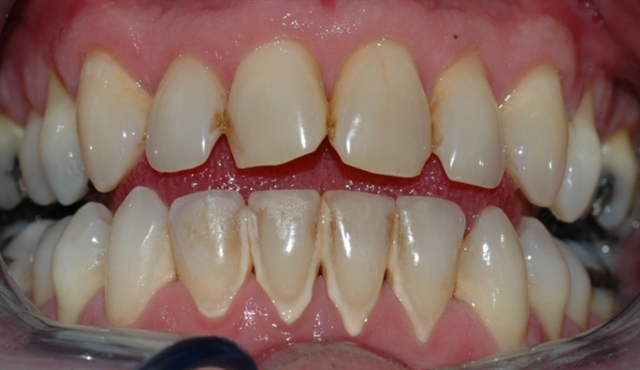

Bildet viser et tannsett med synlig tannsten og misfarging.